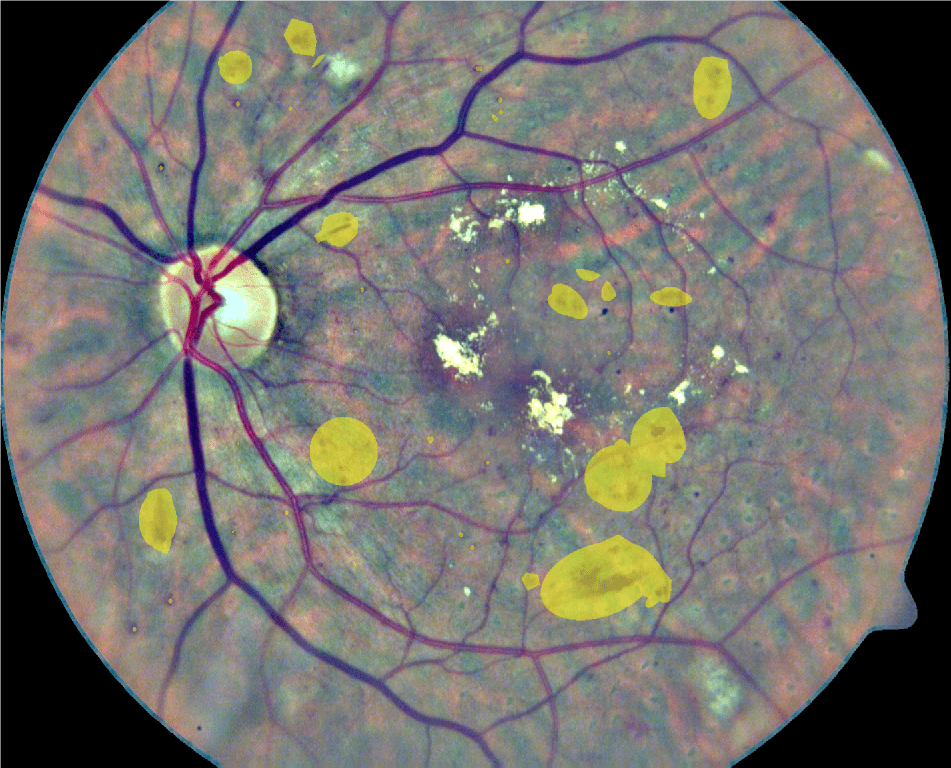

In its early stages, DR might be clinically asymptomatic (Abràmoff et al., 2010). As a consequence, this condition is typically identified when it is more advanced and treatments are significantly less effective (Mookiah et al., 2013). A recent study has shown that 44% of hospitalized patients with diabetes remain undiagnosed (Kovarik et al., 2016). To prevent this, people suffering from diabetes are usually recommended to be regularly examined through fundus images to verify the non-existence of red lesions (Abràmoff et al., 2010). Although fundus photographs are currently the most economical non-invasive imaging technique for this purpose, manual diagnosis requires an intensive effort to screen the images (Mookiah et al., 2013). Red lesions appear as small red dots that might be subtle and too small to be detected at first glance (Figure 1). Large HEs, on the contrary, are more evident and less difficult to visualize.

Finally, qualitative results for a randomly selected image in the DIARETDB1 test set are depicted in Figure 10. Green circles are detected lesions according to the ground truth labeling provided in the data set, while yellow circles correspond to lesions detected by our method but that are not labeled in the ground truth. Finally, red circles surround the lesions that were manually annotated as true lesions but were ignored by the method. Qualitatively, many of the yellow circles appear to be microaneurysms or hemorrhages that were not detected during manual labeling due to their subtle appearance in the original RGB image.